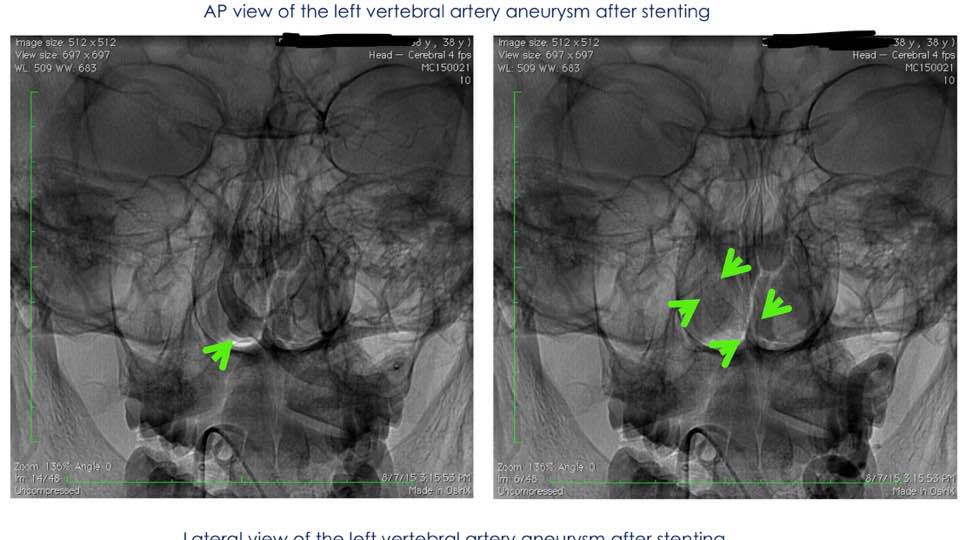

Magnetic resonance imaging showed a cerebral aneurysm of the left vertebral artery about to rupture.

Emergency minimally invasive catheter needle insertion surgery, 1 hour internal vascular treatment, implantation of blood bypass stents to divert blood into fragile cerebral aneurysms, prevent aneurysm rupture and repair blood vessels